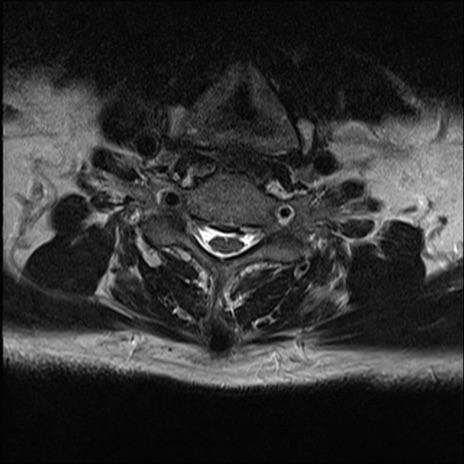

【整形】TIPS症例7 頚椎MRI T2WI(横断像)

頚椎MRI

矢状断像と横断像